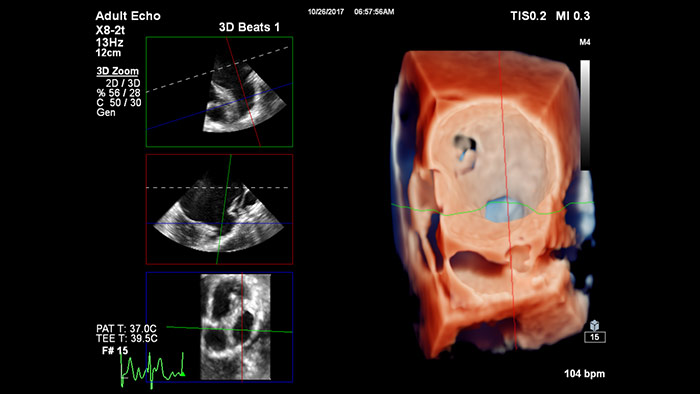

Reproducción con TrueVue con zoom 3D para LAA con visualización MultiVue

Optimización de la vista de la válvula mitral con modelos de corazón EchoNavigator

Optimización de la vista de la válvula tricúspide con modelos de corazón EchoNavigator

Visualización de las válvulas mitral y aórtica con modelos cardíacos EchoNavigator